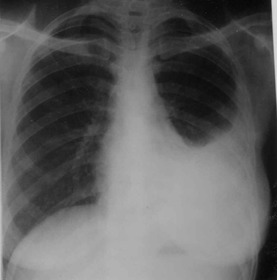

En el 50% de los casos en la radiografía de tórax se observa... Una antigua lesión tuberculosa pulmonar o un patrón miliar.

¿Qué se encuentra en la rx de tórax de un paciente con Tb miliar? Se observa un dibujo retículo nodular miliar, infiltración intersticial y derrames pleurales